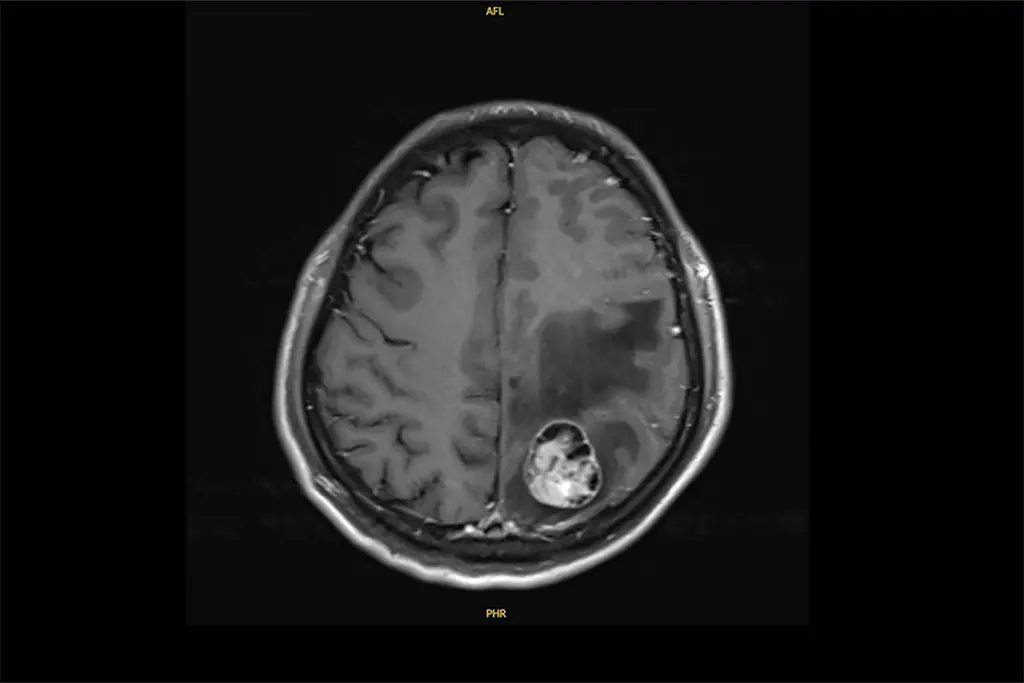

許先生後來出現神經症狀,經胸腔內科、神經外科合作完成腦瘤手術,待術後神經功能恢復,再由胸腔外科進行肺葉切除,達成更徹底控制。